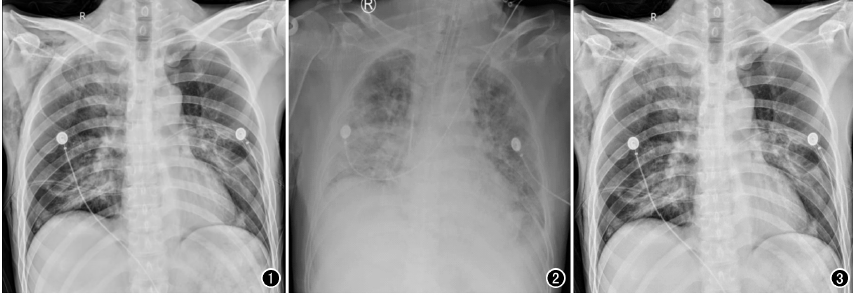

以心臟手術為例,開胸心臟手術多數是在低溫、全麻和體外循環下進行,胸腔創傷較大、風險極高,心臟術后,心外科醫師為了能及時了解術后患者的雙肺復張情況、氣管插管導管頭端位置以及手術并發癥等情況,需要及時對患者進行胸部X線片檢查,以便觀察氣管插管位置,一般來說,插管位置下端應位于第3胸椎水平,過深或者過淺都將影響呼吸機的輔助效果,應確保位置準確,以免影響通氣狀況。另外,包括對于相關手術并發癥的檢查,包括:胸腔積液、氣胸、肺不張等常見問題,需要及時進行胸部X光檢查。相較于幾百萬像素的移動DR,百微移動DR,在圖像質量上顯示更清晰,檢查效率更高,更利于醫生及時進行處置。